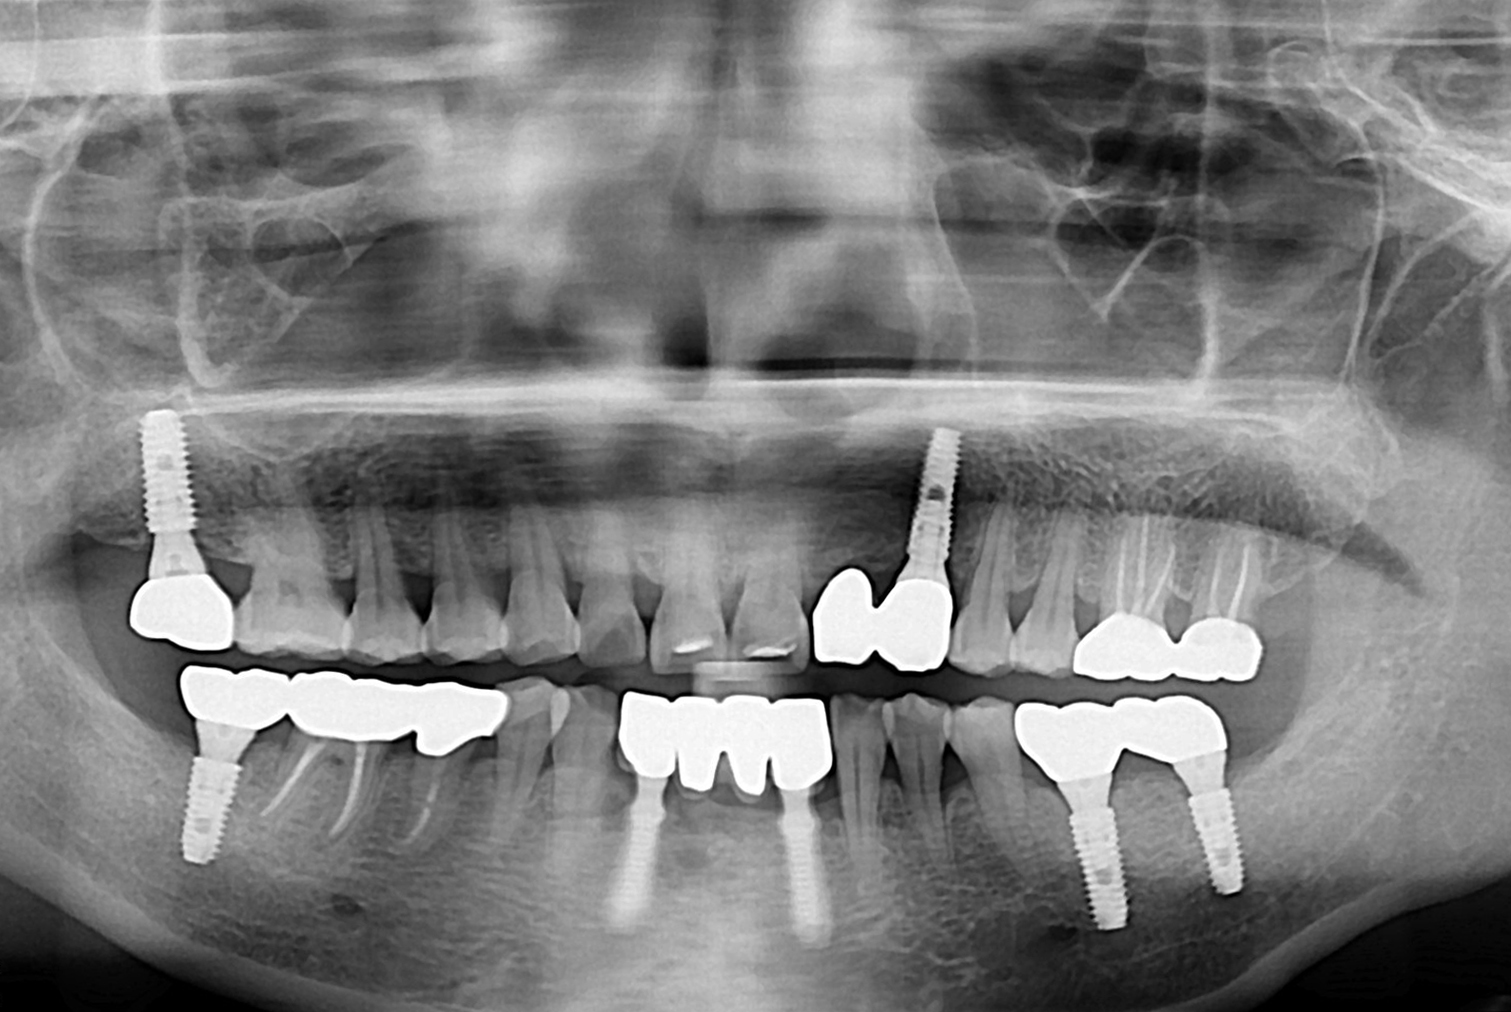

1117김서윤 후.jpg

치료후 : 2019-05-10

세종치과는 많은 환자와 다양한 케이스를 바탕으로 항상 편안한 임플란트 수술을 제공하고자 노력하고,

오래동안 튼튼히 쓸 수 있는 임플란트 수술을 가장 큰 목표로 삼고 있습니다